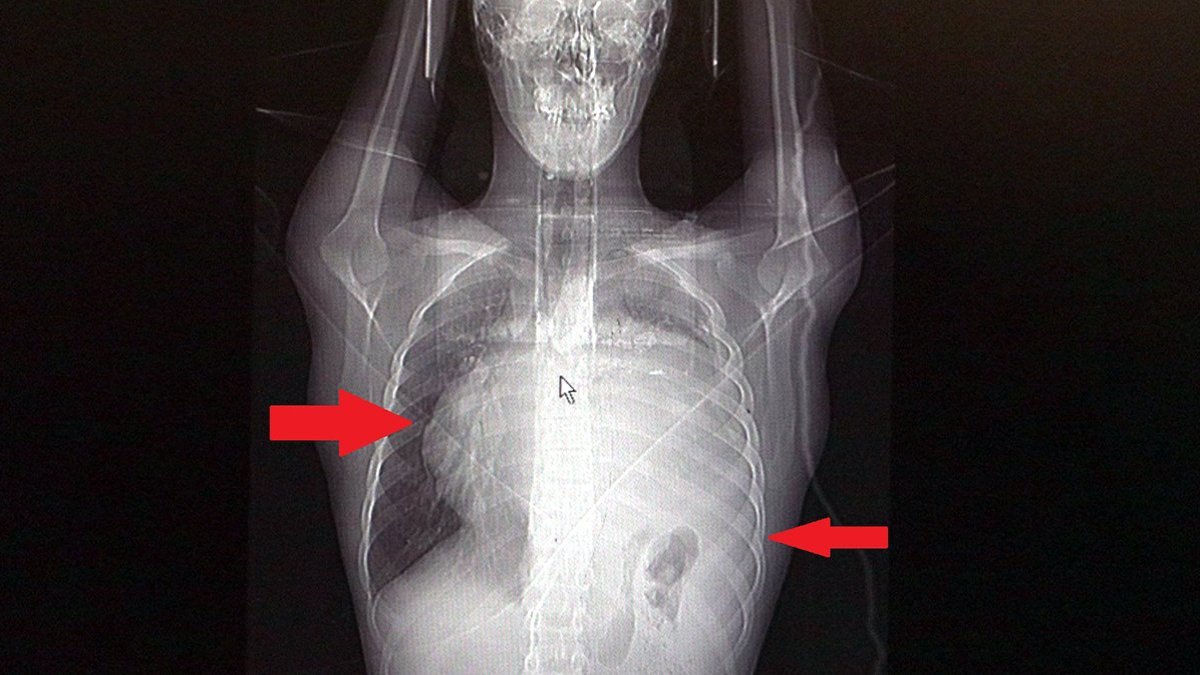

Sol akciğerinin yüzde seksenini kağıt gibi ezen, kalbini göğüs duvarında 12 santim sağa kaydıran ve hem kalbe hem beyne giden ana damarlara baskı yapan 6.5 kilo ağırlığındaki dev tümör, Koşuyolu Yüksek İhtisas Eğitim ve Araştırma Hastanesi Göğüs ve Kalp Damar Cerrahisi ekipleri sayesinde başarılı şekilde çıkarıldı.

Operasyon sırasında Aktaş'ın kalbi normal yerine çekildi, sol akciğerin üst lobu alındı, ezilen alt lobu ise anestezi ekipleri tarafından pozitif basınçla yeniden şişirildi.